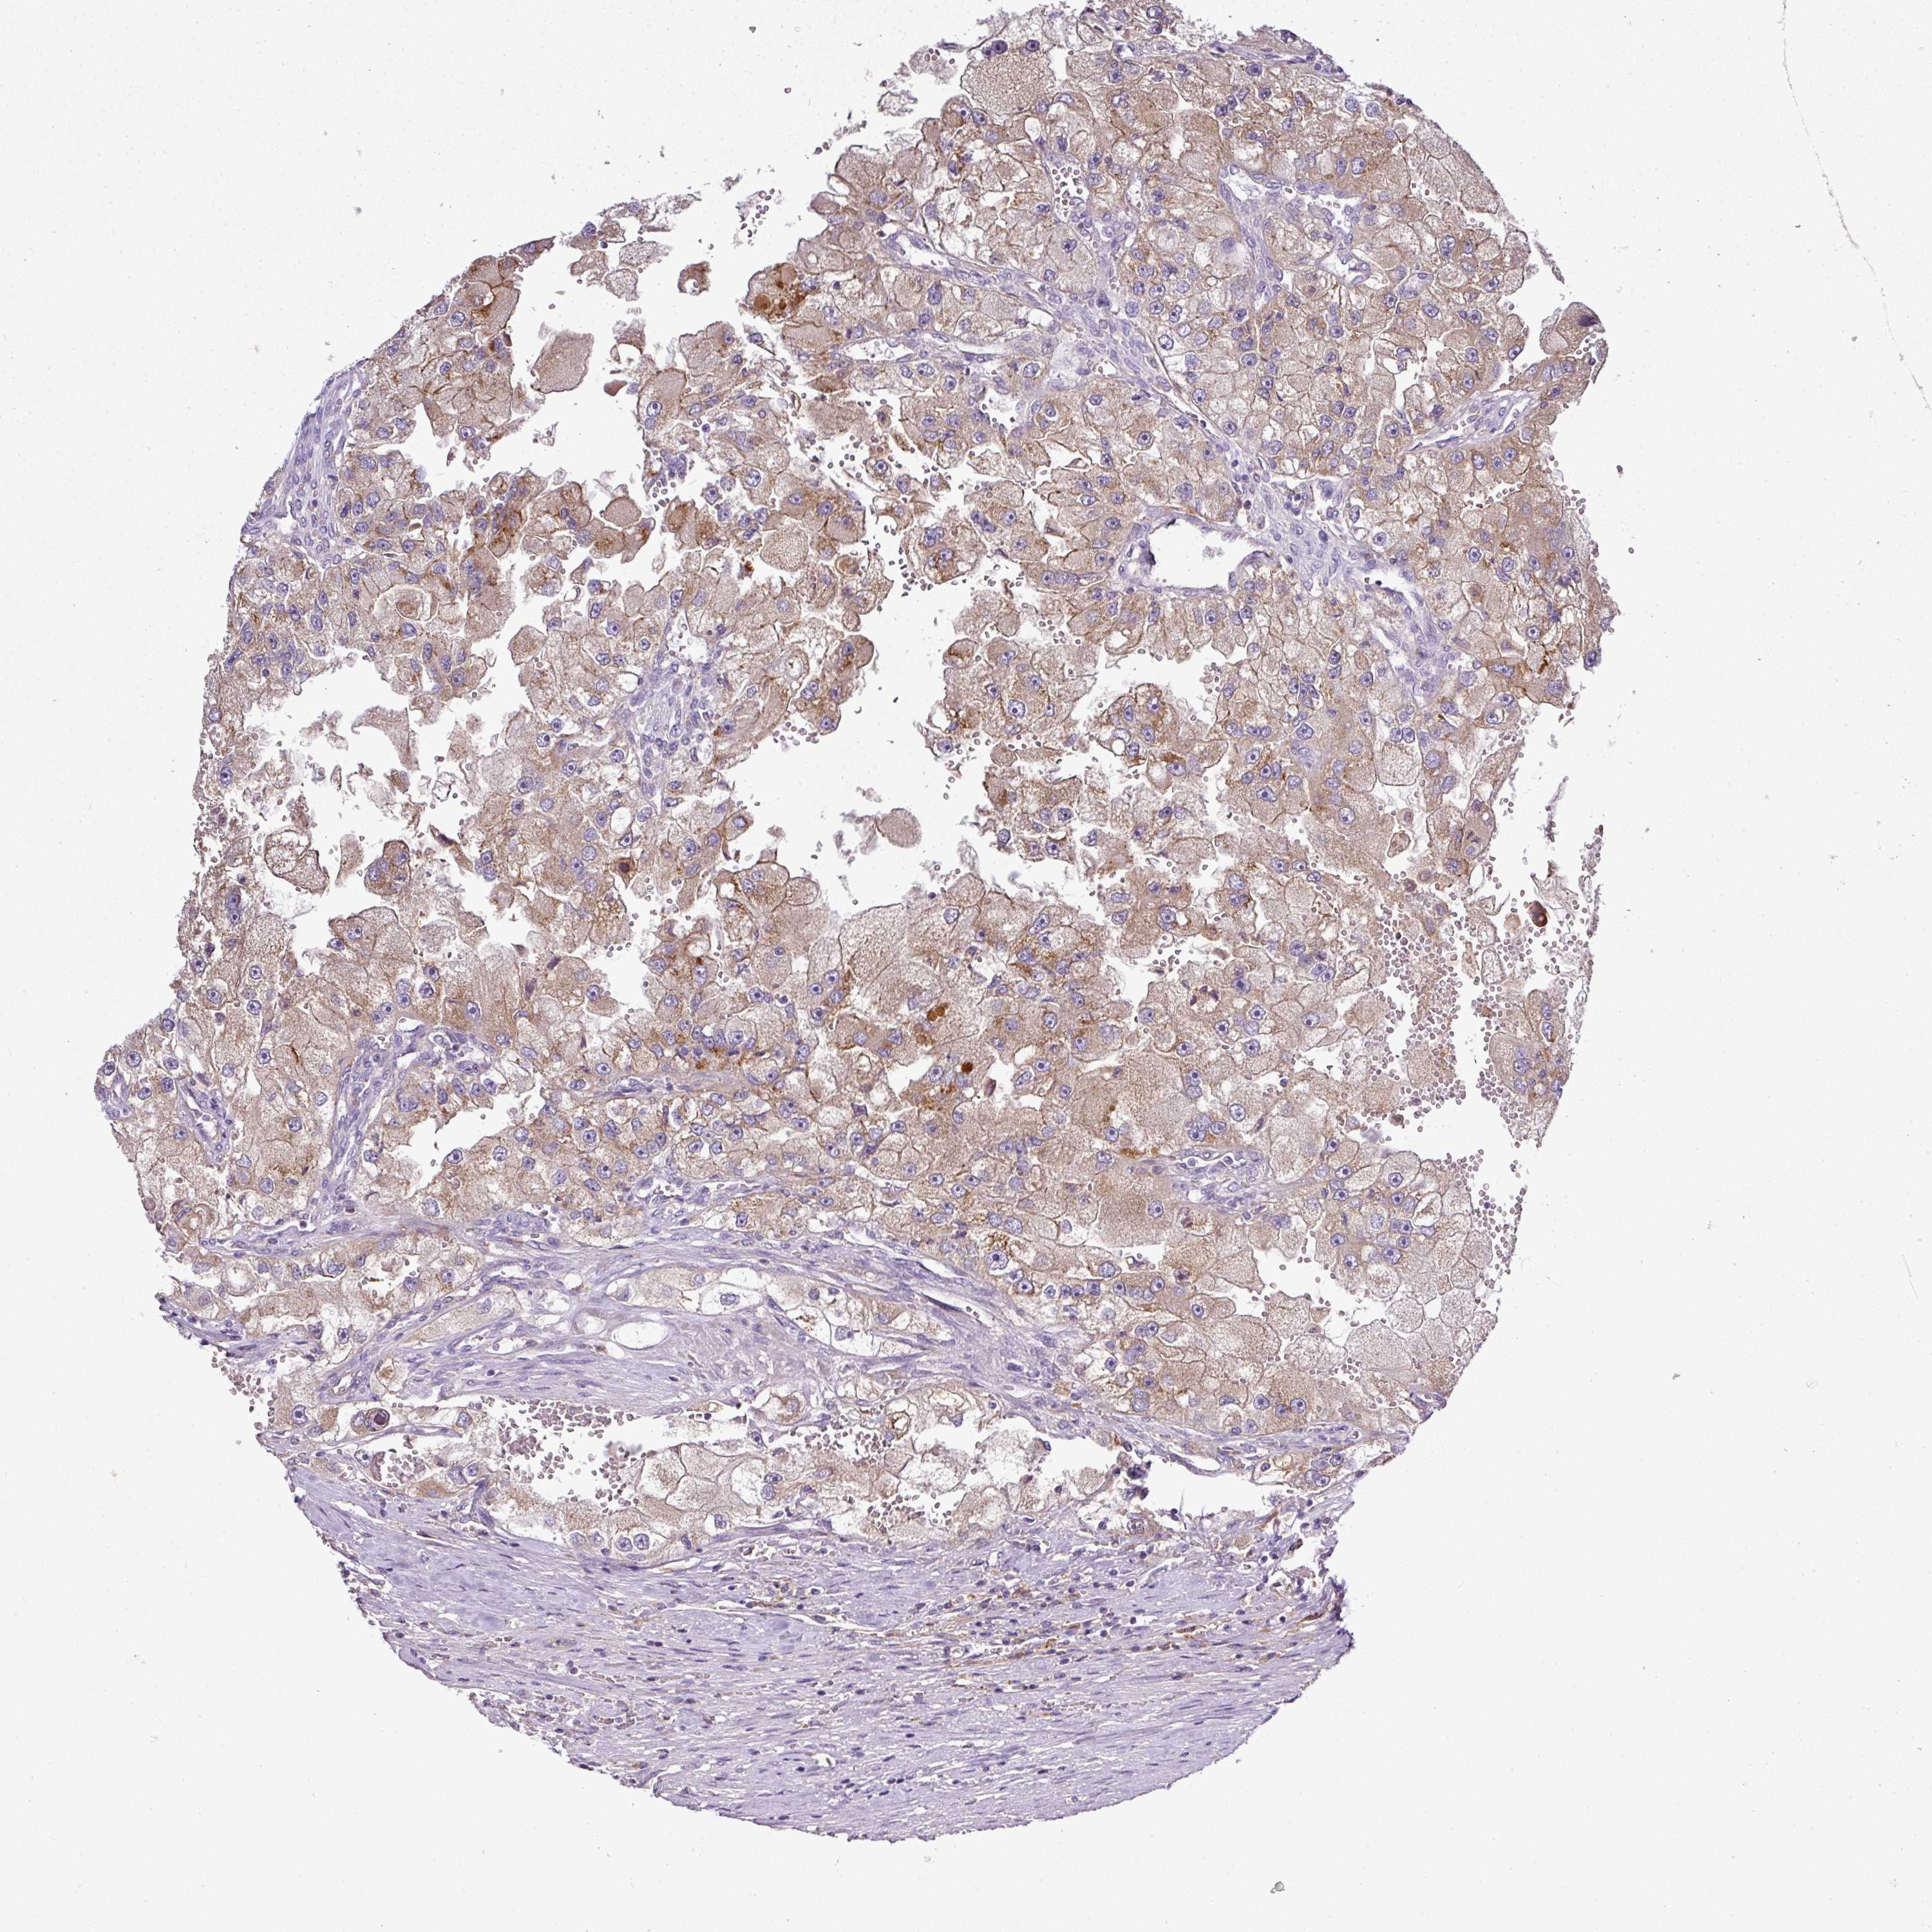

KIDNEY RENAL CLEAR CELL CARCINOMA (TCGA) - Interactive survival scatter ploti

The Survival Scatter plot shows the clinical status (i.e. dead or alive) for all individuals in the patient cohort, based on the same data that underlies the corresponding Kaplan-Meier plots. Patients that are alive at last time for follow-up are shown in blue and patients who have died during the study are shown in red.

The x-axis shows the expression levels (FPKM) of the investigated gene in the tumor tissue at the time of diagnosis. The y-axis shows the follow-up time after diagnosis (years). Both axes are complimented with kernel density curves demonstrating the data density over the axes. The top density plot shows the expression levels (FPKM) distribution among dead (red) and alive patients (blue). The right density plot shows the data density of the survived years of dead patients with high and low expression levels respectively, stratified using the cutoff indicated by the vertical dashed line through the Survival Scatter plot. This cutoff is automatically defined based on the FPKM cutoff that minimizes the p-score. The cutoff can be changed by dragging the vertical line or by entering a cutoff value in the square labeled "Current cut-off".

Under the Survival Scatter plot the p-score landscape (black curve; left axis) is shown together with dead median separation (red curve; right axis). Dead median separation is the difference in median mRNA expression between patients who have died with high and low expression, respectively. It is calculated as follows: median FPKM expression of dead patients with high expression - median FPKM expression of dead patients with low expression. This is intended to aid the user in visually exploring custom cutoffs and the associated p-scores and dead median separation.

Individual patient data is displayed and can be filtered by clicking on one or more of the category buttons on the top of the page. Categories describing expression level and patient information include: high, low, alive, dead, female, male and tumor stages. The scale of the x-axis can be toggled between linear and log-scale by clicking on the "x log" button. Mouse-over function shows TCGA ID, patient information and mRNA expression (FPKM) for each patient.

& Survival analysisi

Kaplan-Meier plots summarize results from analysis of correlation between mRNA expression level and patient survival. Patients were divided based on level of expression into one of the two groups "low" (under cut off) or "high" (over cut off). X-axis shows time for survival (years) and y-axis shows the probability of survival, where 1.0 corresponds to 100 percent.

CAB39L is potential prognostic, high expression is favorable in Kidney Renal Clear Cell Carcinoma (TCGA)

Best expression cut offi

Based on the FPKM value of each gene, patients were classified into two groups and association between prognosis (survival) and gene expression (FPKM) was examined. The best expression cut-off refers the FPKM value that yields maximal difference with regard to survival between the two groups at the lowest log-rank P-value. Best expression cut-off was selected based on survival analysis .

When clicking on this number, the vertical dashed line indicating cut-off, the interactive survival plot, and the Kaplan-Meier curve will be adjusted to show results based on the best expression cut-off.

: 3.83

TCGA RNA samplesi

RNA-seq data is reported as average FPKM (number Fragments Per Kilobase of exon per Million reads), generated by the The Cancer Genome Atlas (TCGA) .

Normal distribution across the dataset is visualized with box plots, shown as median and 25th and 75th percentiles. Points are displayed as outliers if they are above or below 1.5 times the interquartile range. FPKM values of the individual samples are presented next to the box plot.

Average pTPM 6.4

Number of samples 521